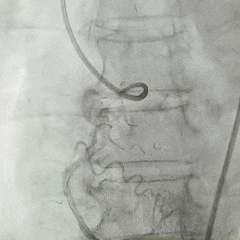

左侧冠脉造影

右侧冠脉造影并行PCI

根部造影

可见瓣叶钙化,伴反流

TF21瓣膜0位初始释放